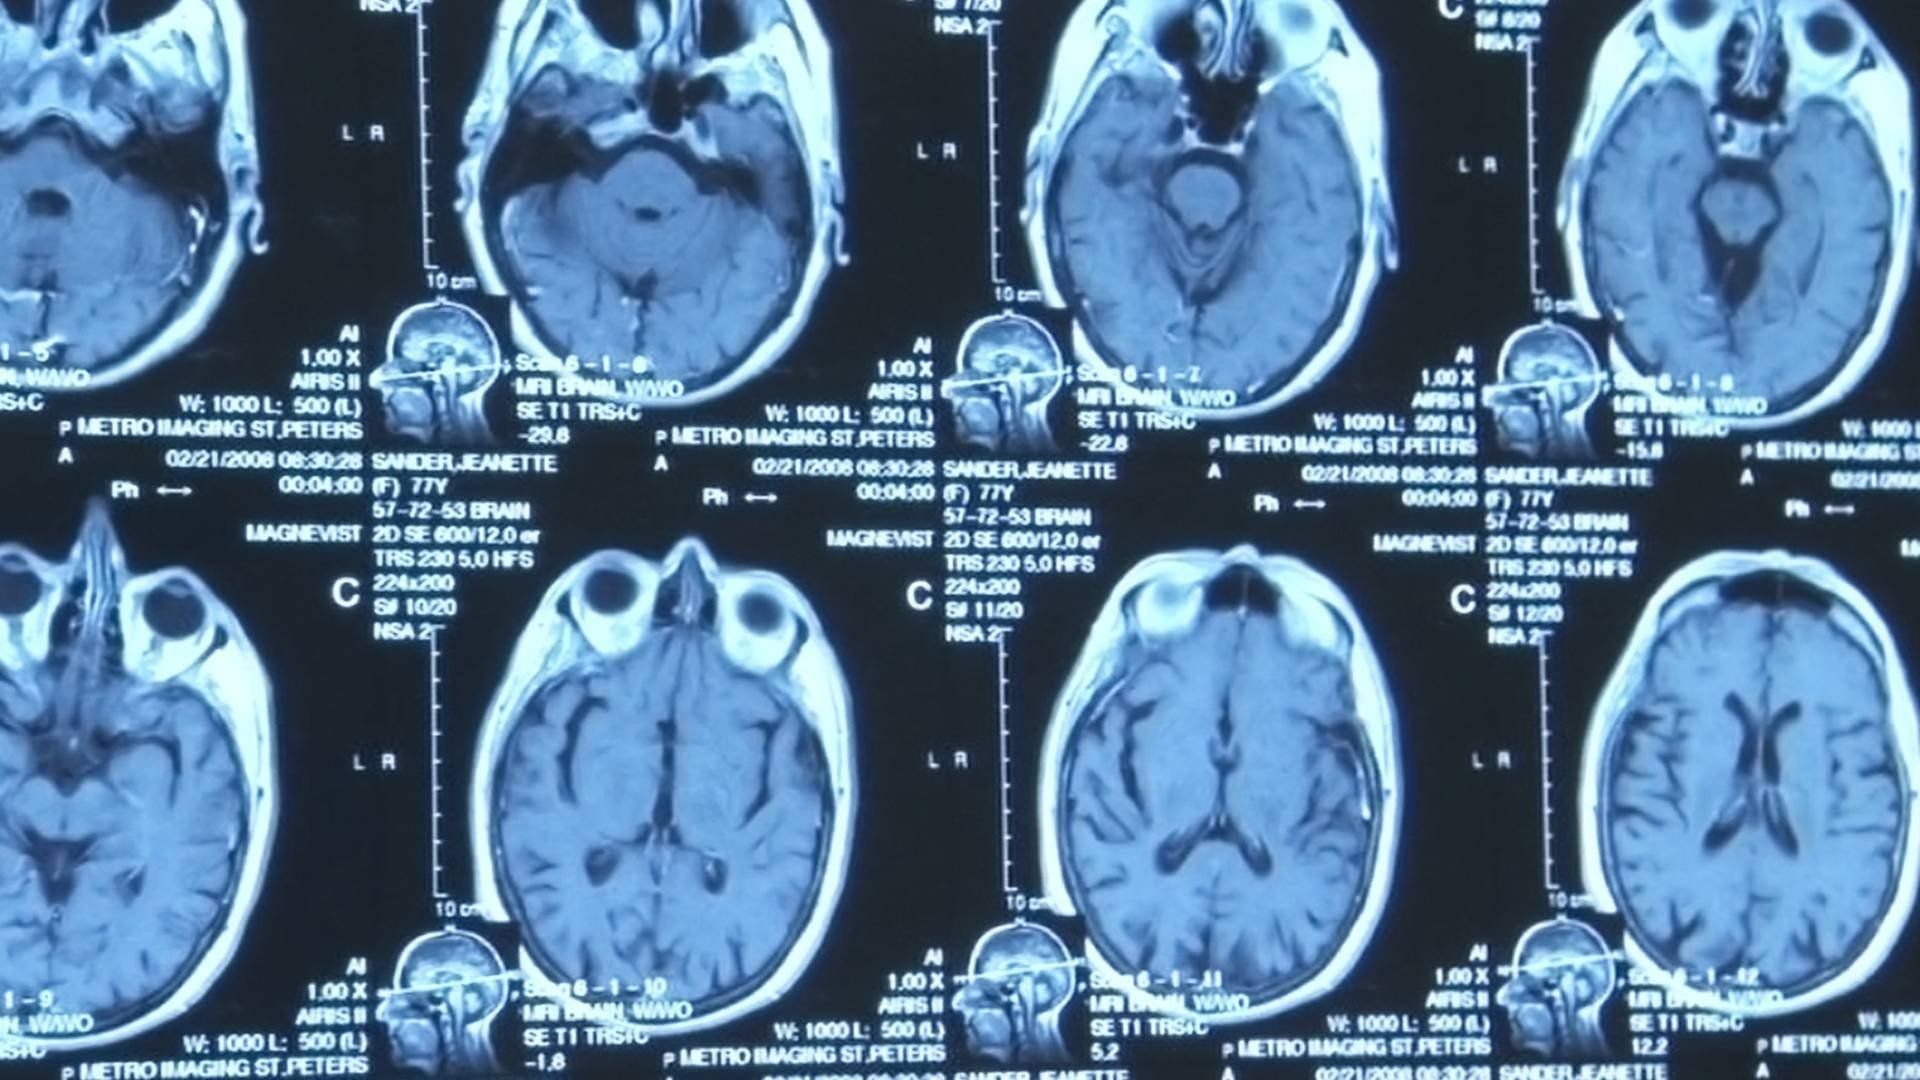

Aired: May 10, 2009A documentary series follows the lives of seven individuals with Alzheimer's ...

The next episode explores the profound emotional toll of Alzheimer's disease on caregivers, showcasing the unwavering bonds of love and resilience as they navigate the difficulties of their loved ones' gradual decline.